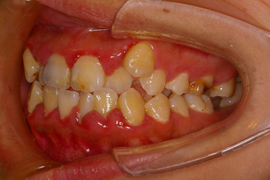

インプラント (女性/早良区)

- 治療前

- 治療後

治療を受けての感想

何年も片方の歯で噛んでいたので両方で噛めるようになって固いものも噛めるようになりインプラント治療をして良かったと思います。

院長のコメント

遠くから来院されて来られた患者さんでした。歯周病の問題があったので(治療前写真を良く見ると前歯のハグキが腫れています。)インプラント治療をする前に歯周病もしっかり治療されたので期間は掛かりましたが、お口全体の健康度もかなり向上されました。

これから何でも固いものを食べられ、より健康になられる事と思います。